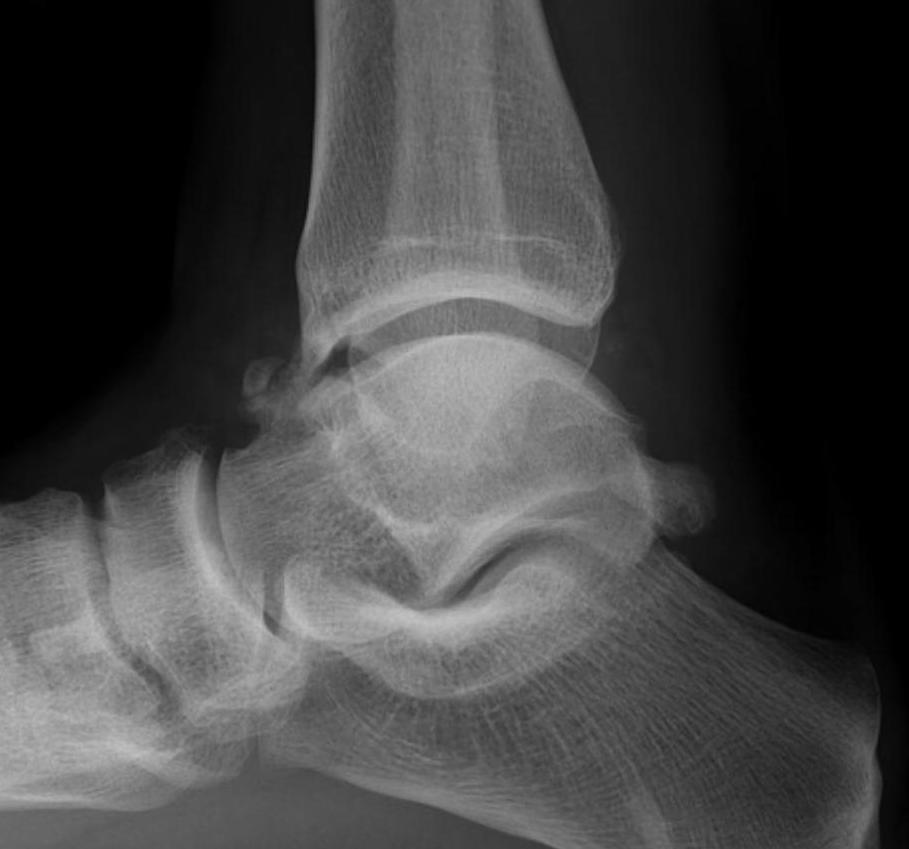

Ankle loose bodies

Loose bodies